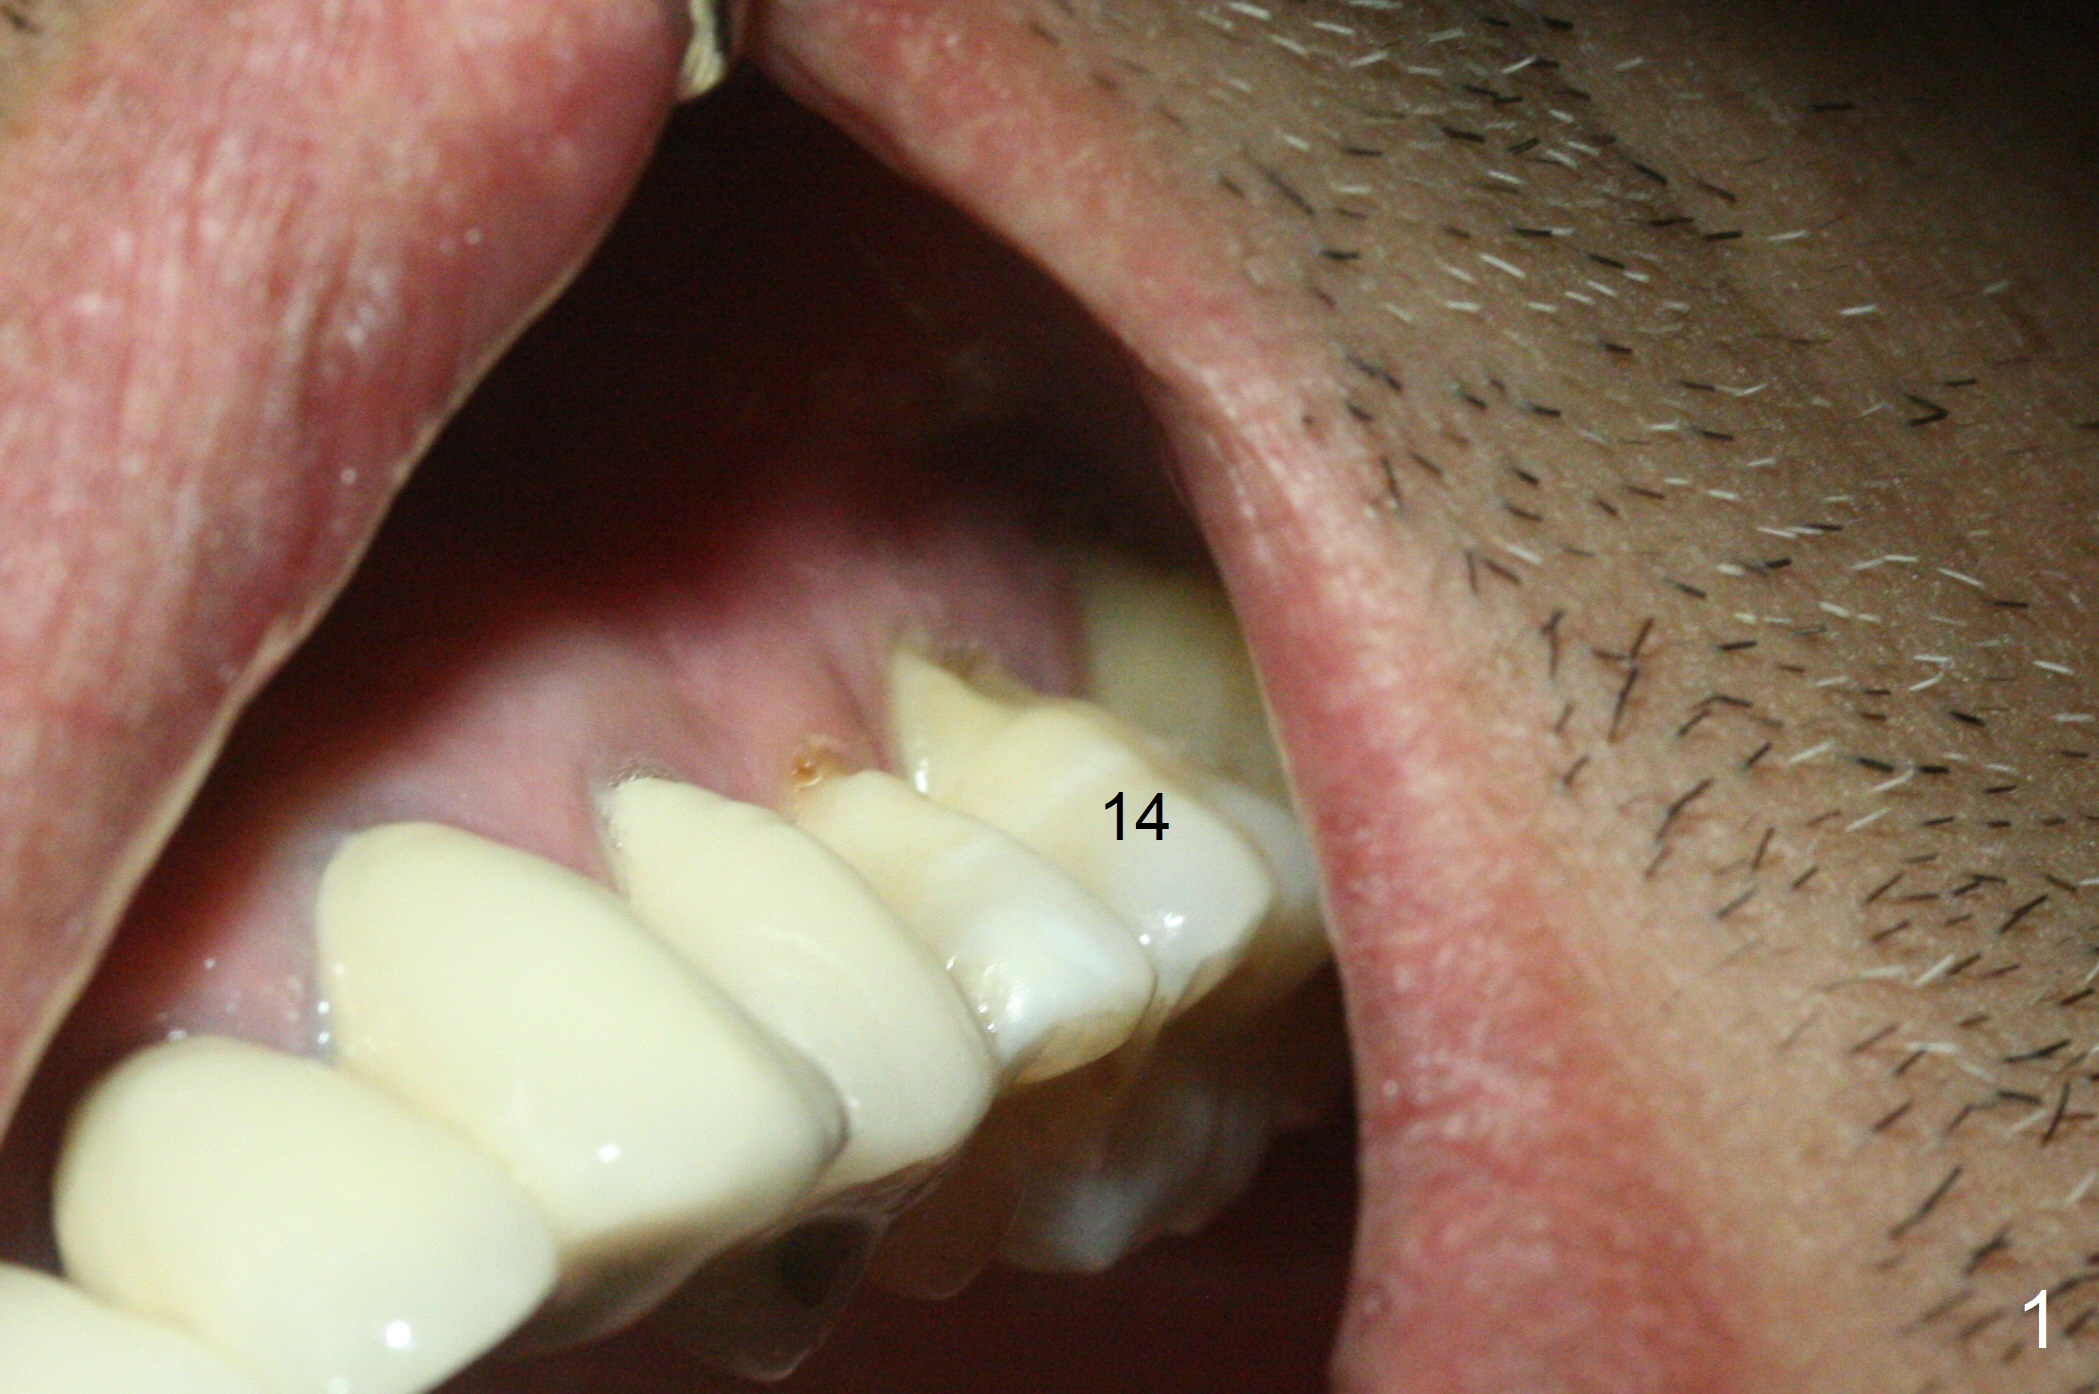

Abutment with 6 mm Cuff A 48-year-old man has mobile, symptomatic upper left 1st molar with severe gingival recession (Fig.1,2, particularly palatal). There appears no sinus floor. The thick gingiva (6 mm (Fig.3 pink)) will dictate a particular implant system. The long clinical crown suggests a long abutment (blue, 7 mm). After extraction and Clindamycin, use the smallest tap drill to initiate osteotomy until stability and sinus lift are achieved. PRF plug (1) and membrane (3) are to be prepared. Return to